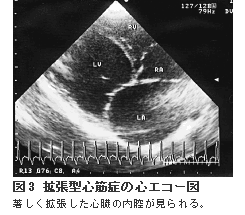

拡張型心筋症は原因不明の心筋の異常によって心臓の収縮する力が弱まり、血液を充分に送り出せなくなってしまう病気です。心臓の内腔は風船のように拡張して見えます。(※図3参照)ドーベルマン、ボクサー、グレートデン、ゴールデンレトリーバー、ラブラドールレトリーバー等の大型犬の雄に多くみられ、雄では雌の2倍以上の発病率が認められています。

診断される時期は4~10歳齢が多いのですが、症状は重度になるまで見られず、発病していても病気が見つかるまでに長い期間が過ぎていることが多いものです。咳、呼吸の回数が多い、呼吸困難、失神、お腹に水が溜まる(腹水)、足先が冷たい等の症状が現れますが、不整脈が発生して突然死してしまう危険性が高い病気です。